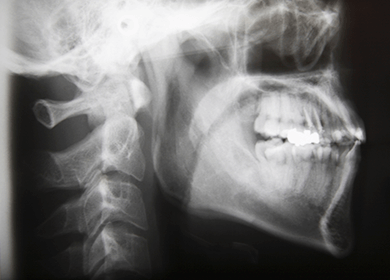

歯科用デジタルレントゲン(オルソパントモ)を使用し、顎の全体像を一度に撮影するため、精密な診断を行うことができます。